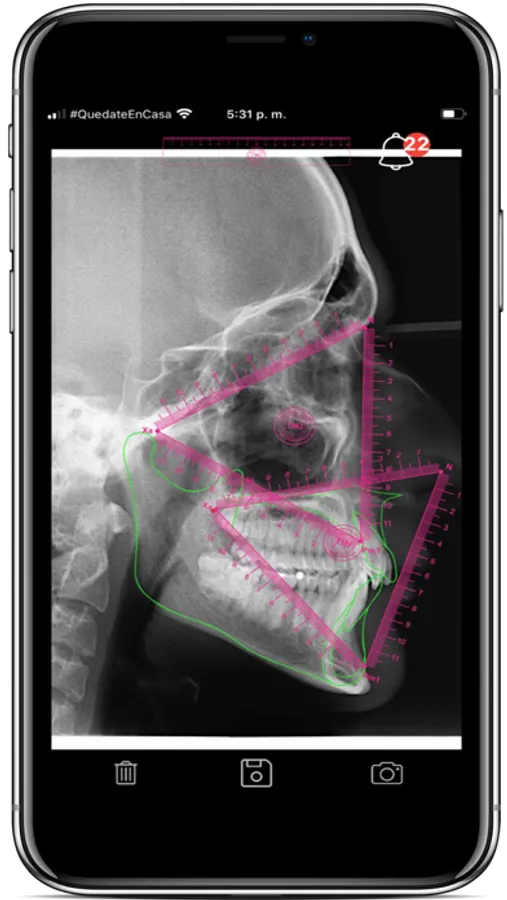

Con innovadoras ideas en el diagnostico creadas por el Dr. Tatis como los los Equilateros Funcionales de Tatis, la Esfera Cráneo-cervical, el auto-trazado dental y esquelético entre otras funciones más, la exactitud y precisión en el diagnóstico estarán garantizadas.

• Análisis cefalométrico de Tatis para la radiografía lateral de cráneo ™

• Equilateros Funcionales de Tatis™

• Esfera cráneo-cervical™

• Trazos personalizados de acuerdo a preferencias del clinico